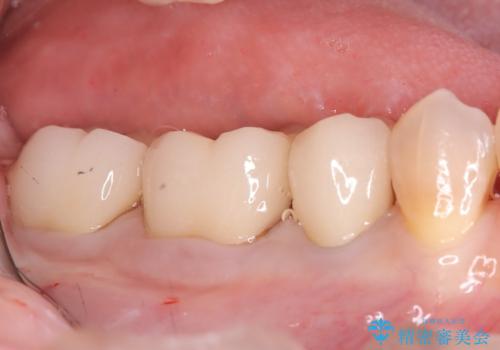

最終的には、左下5・6・7番の3本すべてをセラミッククラウンに置き換え。白くなったことで口元の印象が明るくなり、見た目だけでなく、かみ合わせも良好に仕上がりました。

患者さんからは「ずっと気になっていた銀歯がなくなって、笑うときに気を使わなくてよくなった」とご満足の声をいただきました。定期的なメンテナンスを継続しながら、長期的な機能の維持を図っていきます。